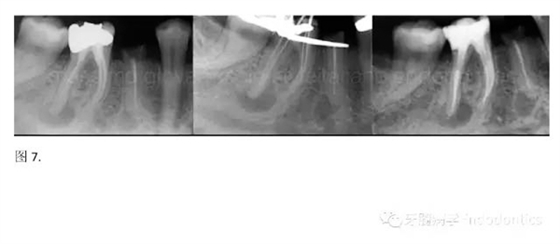

開髓后預(yù)敞、探查根管、建立直線通路是根管機(jī)械預(yù)備的第一步。在這些階段中,醫(yī)生可能會(huì)經(jīng)常遇到一些困難。這些難題包括器械折斷、臺(tái)階形成、根管歧坡或根管拉直、帶狀穿孔、根尖穿孔、根尖肘形、根尖堵塞。所有這些錯(cuò)誤可導(dǎo)致根管系統(tǒng)清潔不完善從而降低牙髓治療成功率。

結(jié)論:本文的目的是描述一種旨在優(yōu)化根管根尖部分預(yù)備的預(yù)敞技術(shù)。根管頸部或冠方的早期預(yù)敞對(duì)于減少初尖銼直徑和根尖部根管直徑之間的差異至關(guān)重要。大量研究表明,手用或機(jī)用器械預(yù)敞根管能顯著減少器械折斷的發(fā)生率。下一篇文章將描述如何建立可重復(fù)的引導(dǎo)路徑。而引導(dǎo)路徑是指鎳鈦器械可沿著光滑根管壁輕易地滑行至工作長度的通路。